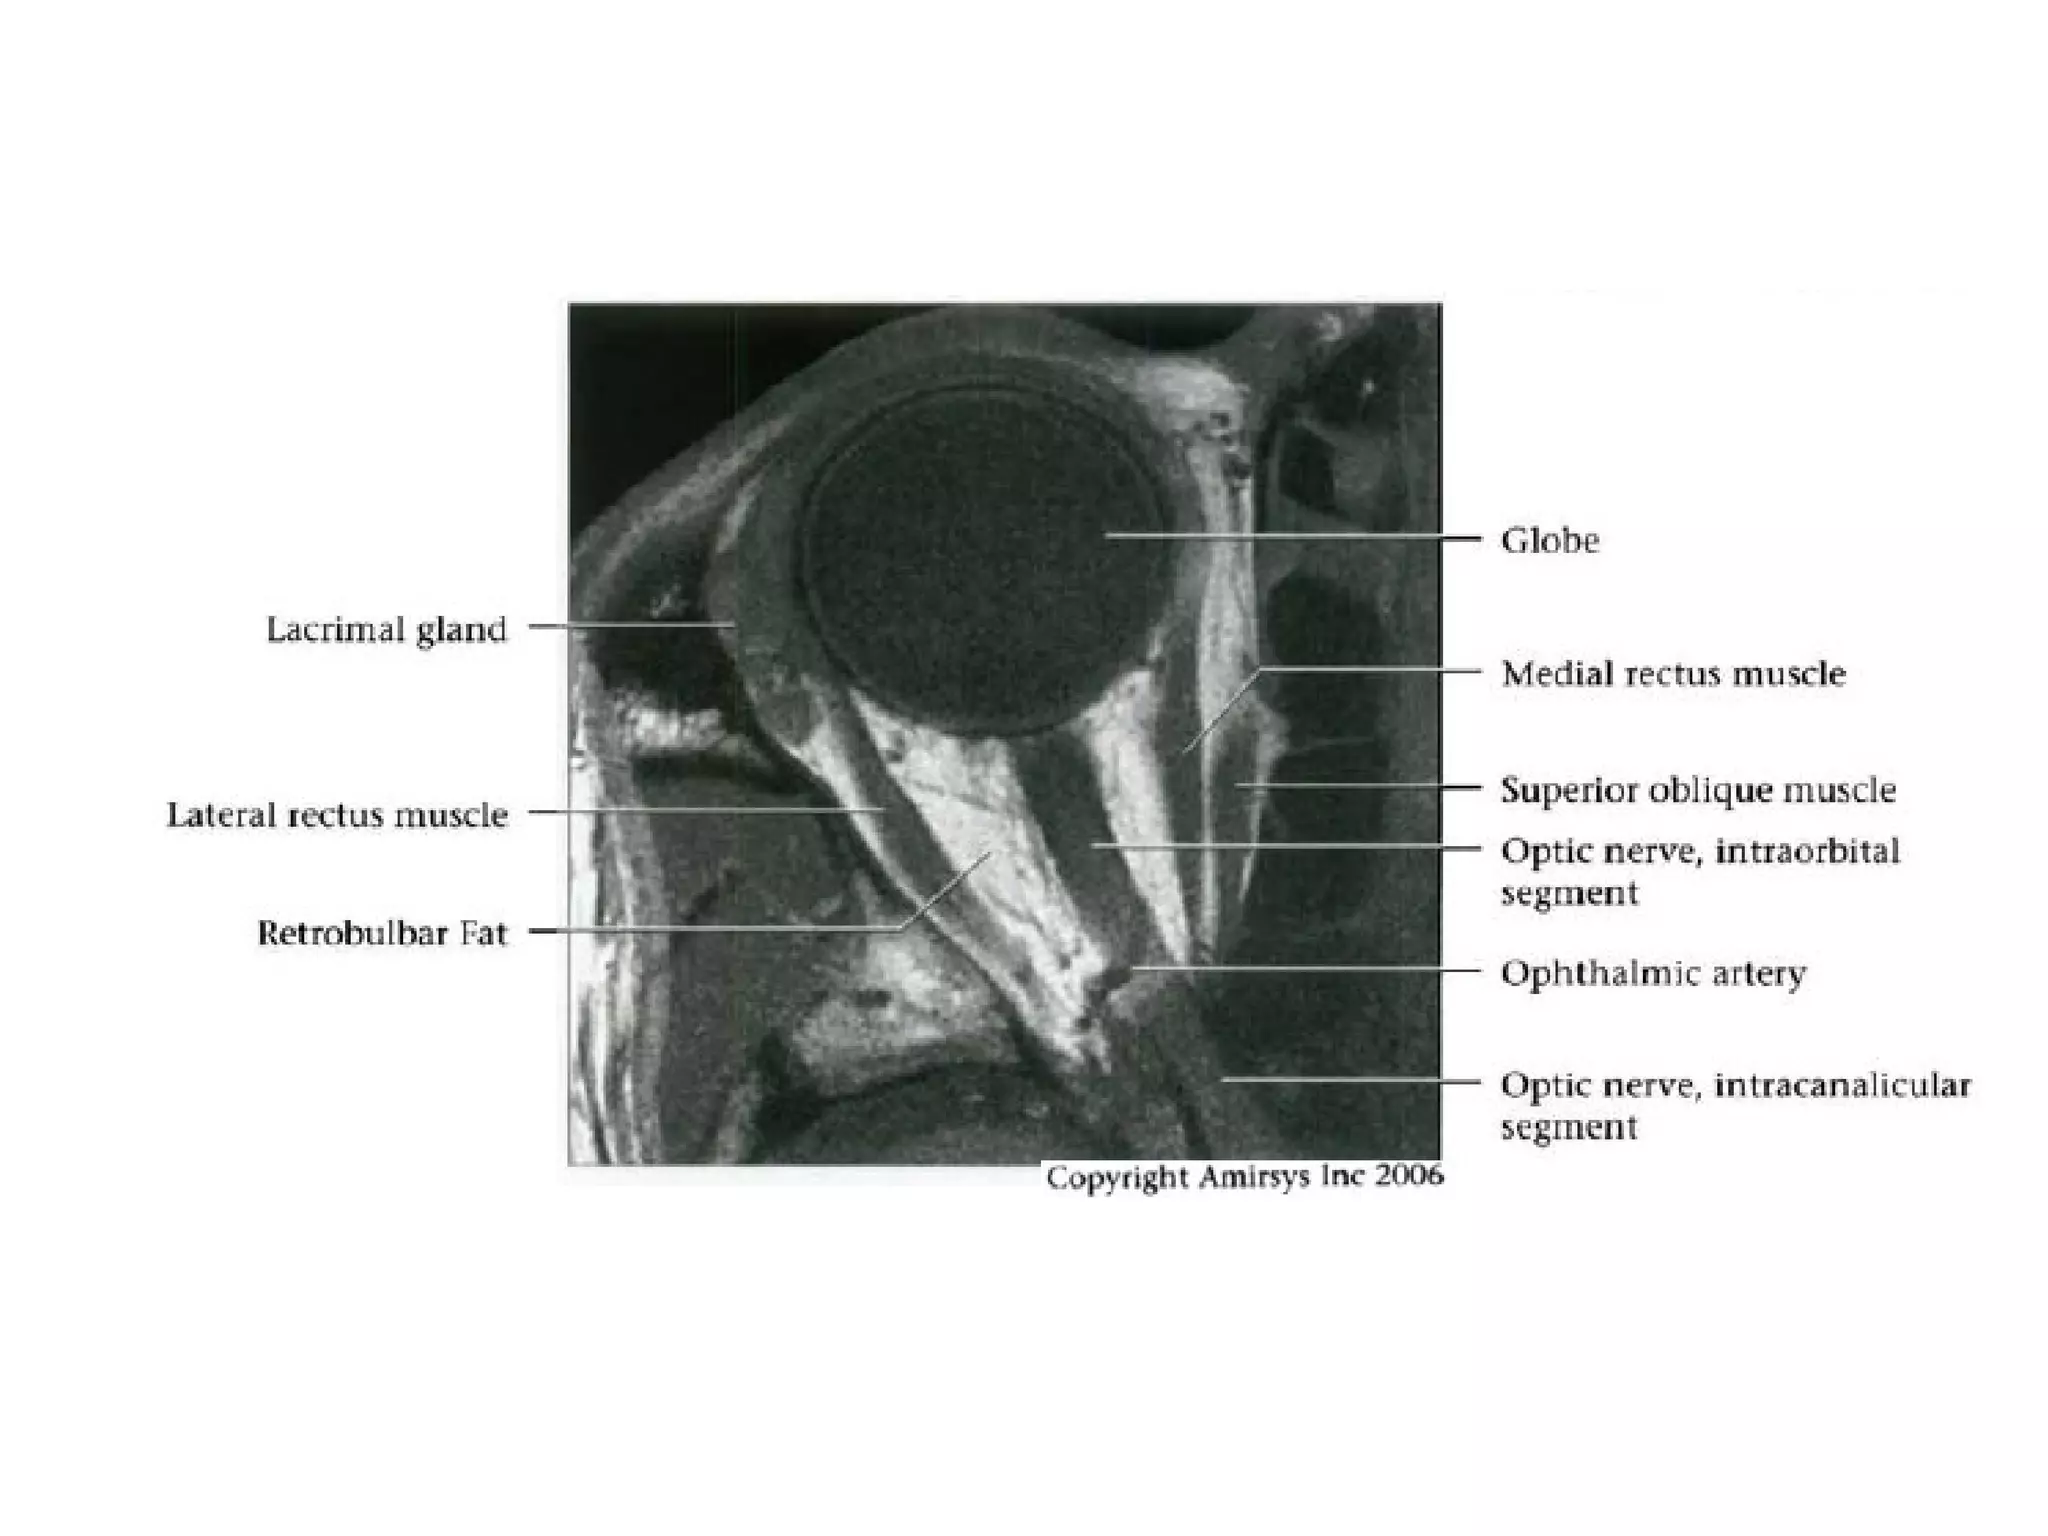

Cranial Nerve II:

The Optic Nerve

• Like the olfactory nerve, the optic nerve is a white-matter tract

without surrounding Schwann cells.

• It includes four anatomic segments: retinal, orbital, canalicular,

and cisternal.

• The retinal segment leaves the ocular globe through the lamina

cribrosa sclerae (the optic foramen of the sclera).

• The orbital segment, which is surrounded by a dural sheath

containing CSF, travels through the center of the fat-filled orbit.

• The canalicular segment is the portion that lies in the optic canal,

below the ophthalmic artery. This segment of the nerve is frequently

overlooked on radiologic images, so it should be specifically sought

when imaging for vision loss.

• Finally, the cisternal segment of the nerve can be visualized in the

suprasellar cistern, where the nerve leads to the optic chiasm. The

anterior cerebral artery passes over the superolateral aspect of the

cisternal segment of the nerve.